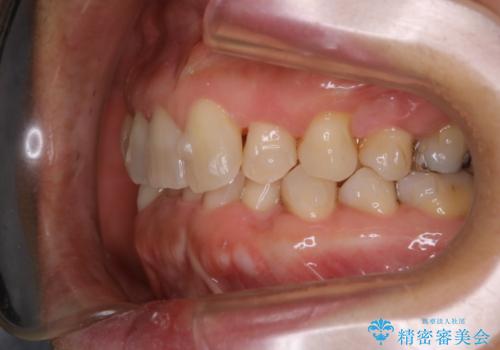

- 上下の歯のがたつきと、噛み合わせが深いことを気にされてご相談にいらした方です。噛み合わせに参加していない歯を抜歯してインビザラインにて治療を行いました。

一般的に噛み合わせの深い方へのインビザライン治療は適応が難しいとされていますが、今回は噛む力を上手にコントロールできたことと、内側に入り込んでいた前歯の角度を調整したことで下の歯がしっかり見えるようになりました。短期間で劇的に見た目が改善し、大変喜んでいただけました。